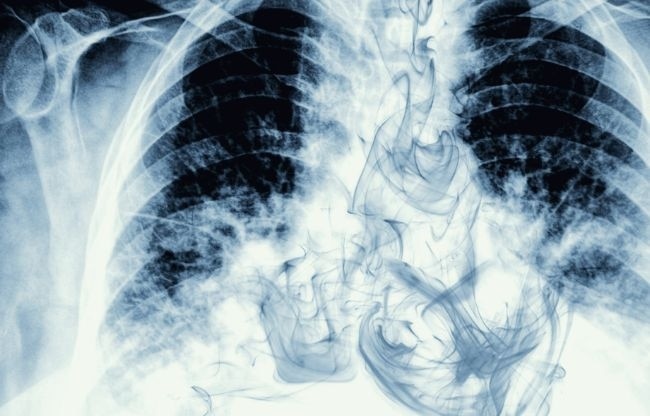

लंग कैंसर को लेकर एक चौंकाने वाली जानकारी सामने आई है. एक नई स्टडी में सामने आया है कि भारत में लंग कैंसर युवाओं में तेजी से फैल रहा है. हैरान करने वाली एक बात ये भी है कि लंग कैंसर के ज्यादातर मरीज वो हैं, जिन्होंने कभी स्मोकिंग नहीं की.

साइंस जर्नल 'लैंसेट' में साउथईस्ट एशिया में लंग कैंसर पर एक स्टडी छपी है. इसमें बताया गया है कि अब लंग कैंसर तेजी से नॉन-स्मोकर्स में भी फैलता जा रहा है.

इस स्टडी के मुताबिक, लंग कैंसर तीसरा सबसे ज्यादा होने वाला कैंसर है. इसमें बताया गया है कि 2020 में दुनियाभर में लंग कैंसर के 22 लाख से ज्यादा नए मामले सामने आए थे, जबकि लगभग 18 लाख लोगों की मौत हो गई थी. वहीं, 2020 में भारत में लंग कैंसर के 72,510 नए मरीज मिले थे और उस साल इससे 66,279 मरीजों की मौत हो गई थी. भारत में 2020 में कैंसर से जितनी मौतें हुईं, उनमें से 7.8% लंग कैंसर के कारण हुई थीं.